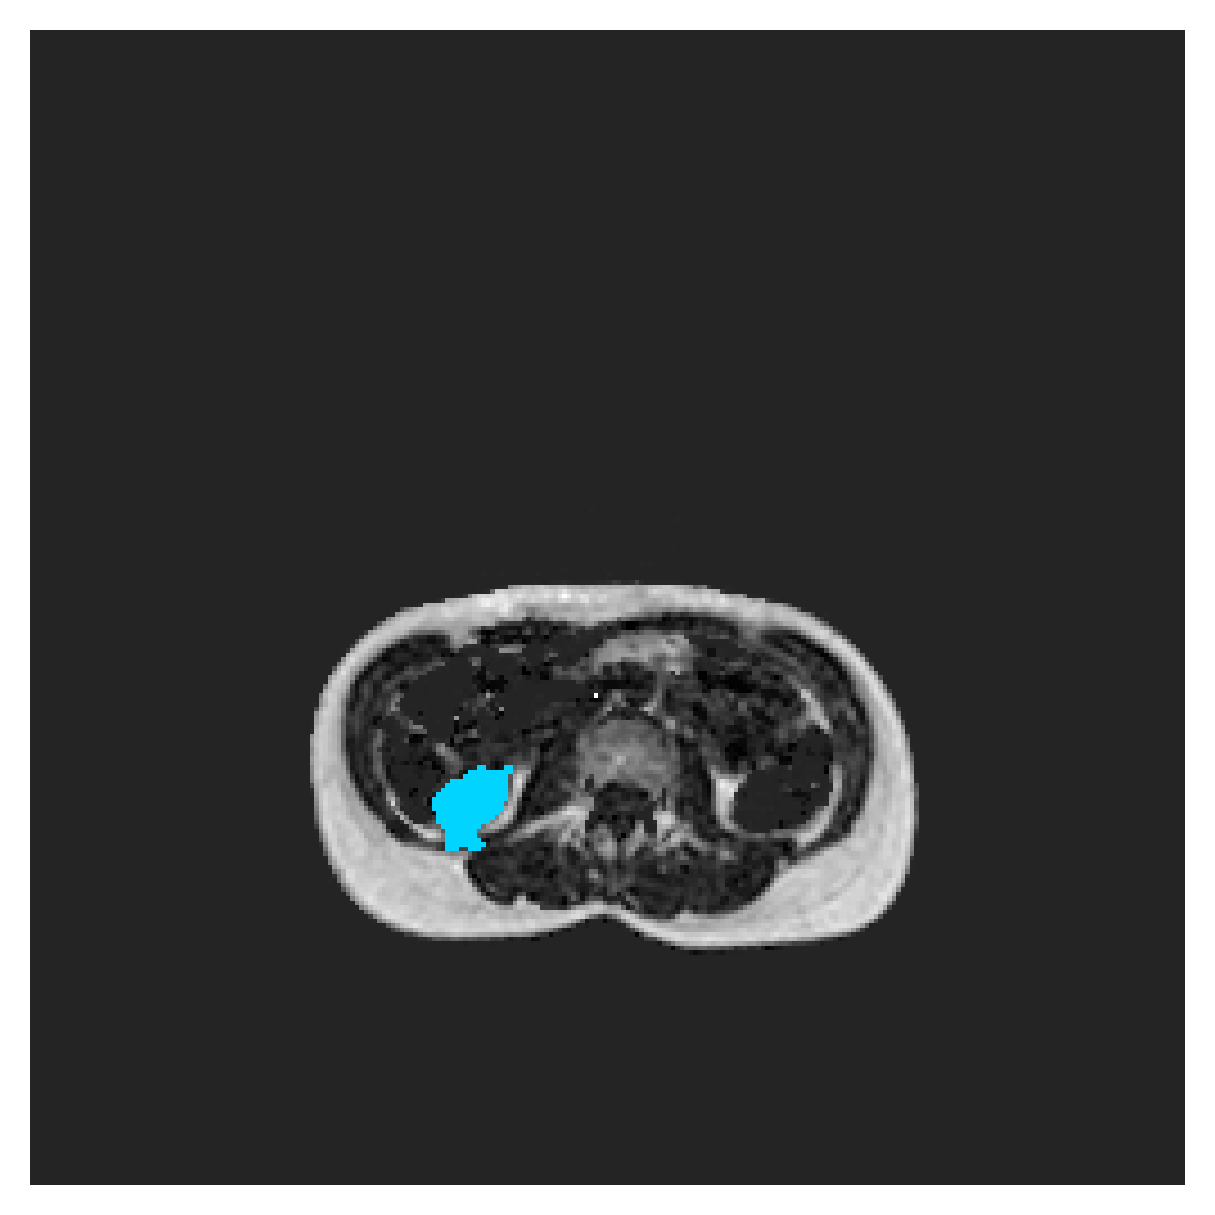

We normalize the volumes and resize the slices to pixels. As the official dataset comes with full annotations, we create a synthetic point ground truth. This is done by first randomly choosing the centers of the point annotations within the class masks, followed by filling an ellipse with axes lengths of and (in pixels) around each center. The intersections of these elliptic discs with the underlying full annotations are then used as our point ground truth. See Figure 2 for an example of the created weak annotation mask. The point annotations are created for every slice, one for each foreground object present in the slice.

The images contain two channels, one for water and one for fat content. For training, we normalize the volumes (per channel) and use 2D slices in the coronal plane, sized . The weak annotations are created synthetically, following the same procedure as described for the ACDC dataset.